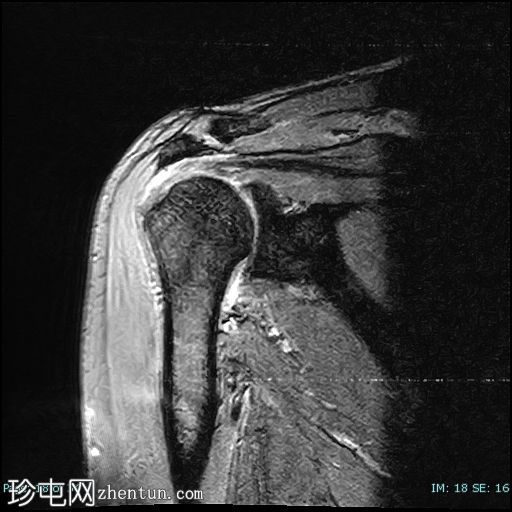

冠状位PD

脂肪抑制

冈上肌腱前部纤维及肌腱止点-关键区交界处全层撕裂。撕裂间隙被T2/PD高信号液体填充。肌腱回缩2.1厘米,位于肩峰水平。

冈上肌腱变薄并伴有肌腱病,冈上肌脂肪变性为2级(Goutallier分级)。

肩胛下肌前外侧纤维肌腱病,无肌腱撕裂。

肩锁关节骨关节炎,伴有骨赘、关节囊增厚、囊性改变、骨髓水肿和关节积液。II型肩峰。无肩峰骨。

本病例展示了退行性冈上肌腱撕裂的典型位置,即肌腱足印和关键区交界处。这与创伤性撕裂(通常发生在肌腱交界处)形成对比。

应注意,不应过度依赖质子密度加权成像序列来诊断肩袖撕裂,因为该序列容易出现魔角伪影,从而模拟撕裂。较长的回波时间序列(例如T2加权成像)可以有效避免这种假阳性结果。